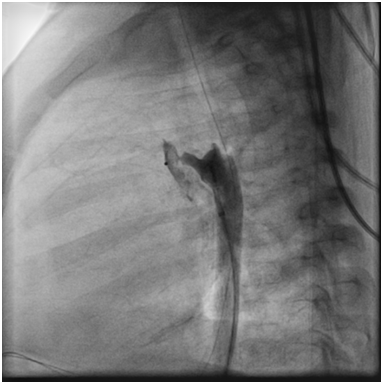

After waiting a few minutes the angiography showed PDA 2mm, with length 9mm (Figure 4).

Figure 4 Angiogram showed the PDA (black arrow).